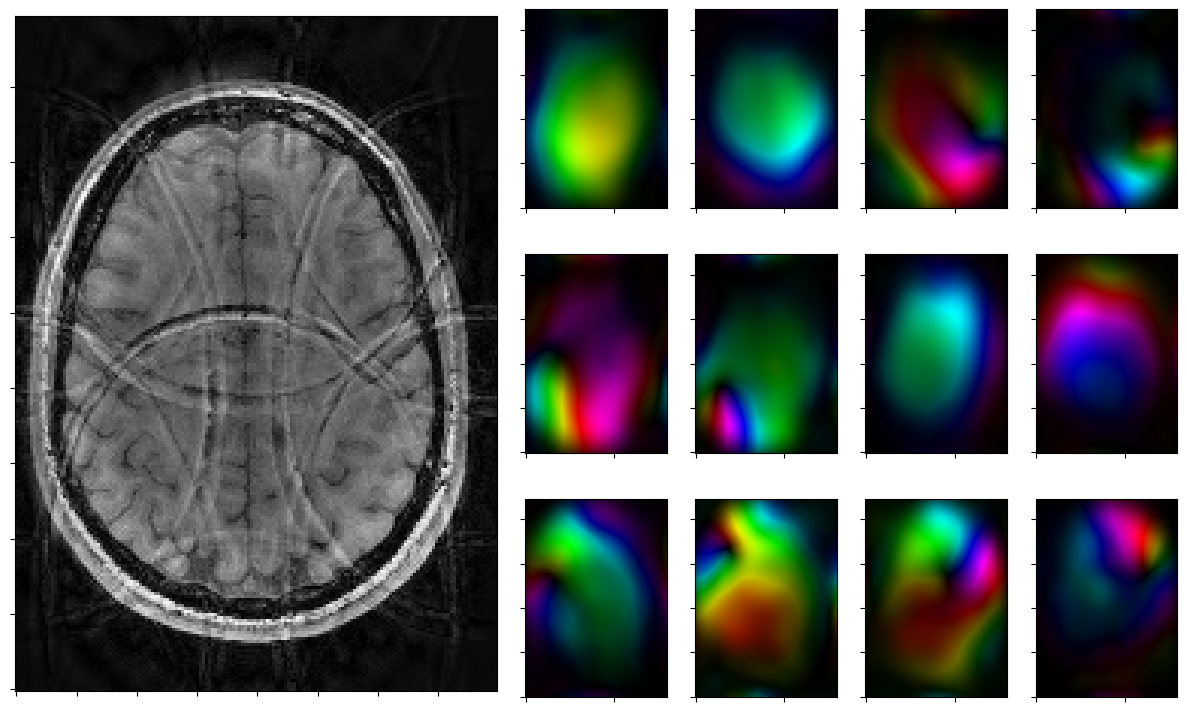

Run solver by hand and plot iterates

Run the solver iteratively and plot each step.

[12]:

for reco, reco_data in solver.while_(stoprule):

rho, coils = smoother.codomain.split(smoother(reco))

#rho, coils = normalize(rho,coils)

fig = plt.figure(figsize = (15,9))

gs = fig.add_gridspec(3,7)

axs = [fig.add_subplot(gs[0:3, 0:3])]

axs[0].imshow(np.abs(rho),cmap=mplib.colormaps['Greys_r'],origin='lower')

axs[0].xaxis.set_ticklabels([])

axs[0].yaxis.set_ticklabels([])

for j in range(3):

for k in range(3,7):

axs.append(fig.add_subplot(gs[j,k]))

axs[-1].xaxis.set_ticklabels([])

axs[-1].yaxis.set_ticklabels([])

for j in range(nrcoils):

axs[1+j].imshow(complex_to_rgb(coils[j,:,:]),origin='lower')

plt.show()

2026-01-29 15:10:13,966 INFO     CountIterations      :: it. 3>=5

2026-01-29 15:10:14,089 INFO     CombineRules         :: it. 0>=1000 | ((rel X:--(x=0)! | rel Y:--(y=0) ) & kappa:1.0e+00) | it. 0>=1000

2026-01-29 15:10:14,161 INFO     CombineRules         :: it. 1>=1000 | ((rel X:2.2e+02>=2.5e-01  | rel Y:1.1e+01>=2.5e-01 ) & kappa:1.4e+00) | it. 1>=1000

2026-01-29 15:10:14,236 INFO     CombineRules         :: it. 2>=1000 | ((rel X:7.7e+01>=2.5e-01  | rel Y:5.0e+00>=2.5e-01 ) & kappa:1.4e+00) | it. 2>=1000

2026-01-29 15:10:14,309 INFO     CombineRules         :: it. 3>=1000 | ((rel X:4.0e+01>=2.5e-01  | rel Y:3.0e+00>=2.5e-01 ) & kappa:1.6e+00) | it. 3>=1000

2026-01-29 15:10:14,381 INFO     CombineRules         :: it. 4>=1000 | ((rel X:2.5e+01>=2.5e-01  | rel Y:2.0e+00>=2.5e-01 ) & kappa:1.9e+00) | it. 4>=1000

2026-01-29 15:10:14,454 INFO     CombineRules         :: it. 5>=1000 | ((rel X:1.8e+01>=2.5e-01  | rel Y:1.5e+00>=2.5e-01 ) & kappa:2.5e+00) | it. 5>=1000

2026-01-29 15:10:14,536 INFO     CombineRules         :: it. 6>=1000 | ((rel X:1.4e+01>=2.5e-01  | rel Y:1.2e+00>=2.5e-01 ) & kappa:3.2e+00) | it. 6>=1000

2026-01-29 15:10:14,609 INFO     CombineRules         :: it. 7>=1000 | ((rel X:1.1e+01>=2.5e-01  | rel Y:1.0e+00>=2.5e-01 ) & kappa:3.6e+00) | it. 7>=1000

2026-01-29 15:10:14,679 INFO     CombineRules         :: it. 8>=1000 | ((rel X:8.6e+00>=2.5e-01  | rel Y:9.1e-01>=2.5e-01 ) & kappa:4.3e+00) | it. 8>=1000

2026-01-29 15:10:14,751 INFO     CombineRules         :: it. 9>=1000 | ((rel X:6.9e+00>=2.5e-01  | rel Y:8.0e-01>=2.5e-01 ) & kappa:5.0e+00) | it. 9>=1000

2026-01-29 15:10:14,823 INFO     CombineRules         :: it. 10>=1000 | ((rel X:5.7e+00>=2.5e-01  | rel Y:7.2e-01>=2.5e-01 ) & kappa:5.3e+00) | it. 10>=1000

2026-01-29 15:10:14,927 INFO     CombineRules         :: it. 11>=1000 | ((rel X:4.8e+00>=2.5e-01  | rel Y:6.5e-01>=2.5e-01 ) & kappa:5.6e+00) | it. 11>=1000

2026-01-29 15:10:14,998 INFO     CombineRules         :: it. 12>=1000 | ((rel X:4.1e+00>=2.5e-01  | rel Y:5.9e-01>=2.5e-01 ) & kappa:5.7e+00) | it. 12>=1000

2026-01-29 15:10:15,070 INFO     CombineRules         :: it. 13>=1000 | ((rel X:3.5e+00>=2.5e-01  | rel Y:5.3e-01>=2.5e-01 ) & kappa:5.4e+00) | it. 13>=1000

2026-01-29 15:10:15,142 INFO     CombineRules         :: it. 14>=1000 | ((rel X:3.0e+00>=2.5e-01  | rel Y:4.8e-01>=2.5e-01 ) & kappa:5.4e+00) | it. 14>=1000

2026-01-29 15:10:15,217 INFO     CombineRules         :: it. 15>=1000 | ((rel X:2.6e+00>=2.5e-01  | rel Y:4.3e-01>=2.5e-01 ) & kappa:5.2e+00) | it. 15>=1000

2026-01-29 15:10:15,292 INFO     CombineRules         :: it. 16>=1000 | ((rel X:2.2e+00>=2.5e-01  | rel Y:3.9e-01>=2.5e-01 ) & kappa:5.7e+00) | it. 16>=1000

2026-01-29 15:10:15,485 INFO     CombineRules         :: it. 17>=1000 | ((rel X:2.0e+00>=2.5e-01  | rel Y:3.6e-01>=2.5e-01 ) & kappa:6.2e+00) | it. 17>=1000

2026-01-29 15:10:15,559 INFO     CombineRules         :: it. 18>=1000 | ((rel X:1.8e+00>=2.5e-01  | rel Y:3.3e-01>=2.5e-01 ) & kappa:7.4e+00) | it. 18>=1000

2026-01-29 15:10:15,630 INFO     CombineRules         :: it. 19>=1000 | ((rel X:1.6e+00>=2.5e-01  | rel Y:3.1e-01>=2.5e-01 ) & kappa:7.4e+00) | it. 19>=1000

2026-01-29 15:10:15,702 INFO     CombineRules         :: it. 20>=1000 | ((rel X:1.5e+00>=2.5e-01  | rel Y:2.9e-01>=2.5e-01 ) & kappa:7.6e+00) | it. 20>=1000

2026-01-29 15:10:15,776 INFO     CombineRules         :: it. 21>=1000 | ((rel X:1.3e+00>=2.5e-01  | rel Y:2.7e-01>=2.5e-01 ) & kappa:8.5e+00) | it. 21>=1000

2026-01-29 15:10:15,862 INFO     CombineRules         :: it. 22>=1000 | ((rel X:1.2e+00>=2.5e-01  | rel Y:2.5e-01>=2.5e-01 ) & kappa:9.2e+00) | it. 22>=1000

2026-01-29 15:10:15,932 INFO     CombineRules         :: it. 23>=1000 | ((rel X:1.1e+00>=2.5e-01  | rel Y:2.4e-01>=2.5e-01 [Rule RelTolYStop(0.3333333333333333) triggered.]) & kappa:8.9e+00[All rules triggered.]) | it. 23>=1000

../_images/notebooks_parallel_mri_21_7.png